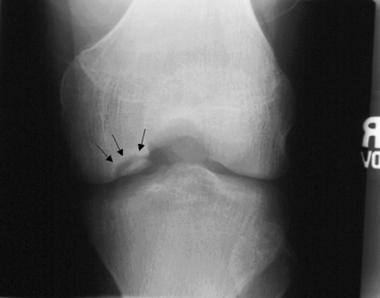

​L’osteocondrite è una patologia del ginocchio che coinvolge un frammento osteocondrale (cartilagine e osso sottostante) di grandezza e localizzazione variabili

osteocondrite del ginocchio

Frammento osteocondrale

La posizione tipica delle osteocondriti al ginocchio è il terzo laterale del condilo femorale mediale (85%) e solitamente sono di dimensioni medio-grandi (da 1.5 cm a 4 cm di diametro). Meno frequenti sono le lesioni al condilo laterale (13%), alla troclea femorale (2%) e alla rotula (<1%).